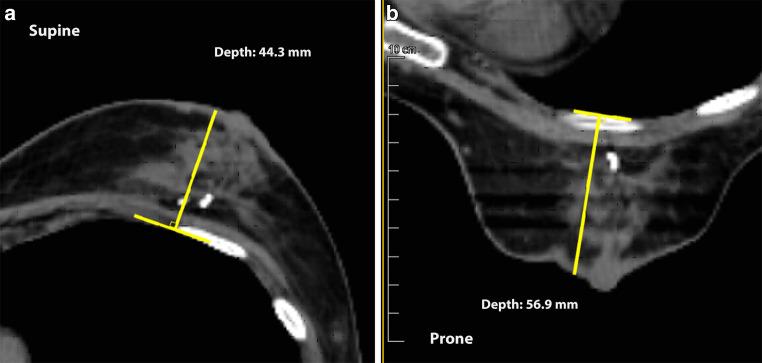

Among 116 patients identified with dual CT planning, the prone setup, compared with supine, was associated with a dosimetric gain in 72 (62.1%, 95% CI: 52.6-70.9%). The most significant predictors of a gain with the prone setup were the breast depth prone/supine ratio (>1.6), breast depth difference (>31 mm), prone breast depth (>77 mm), and breast volume (>282 mL).

Prone compared with supine DiBH was associated with a dosimetric gain in 62.1% of our left-sided breast cancer patients. High pendulousness and moderately large breast predicted for the gain.